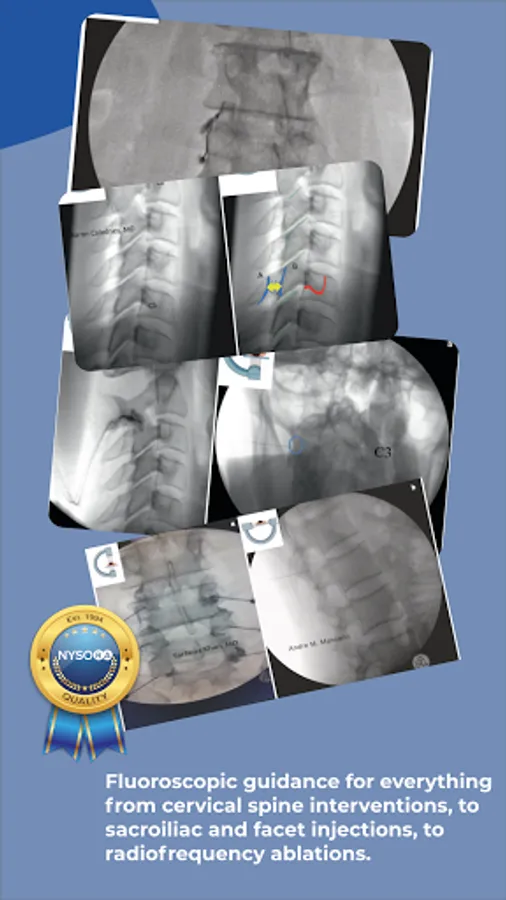

Standardized Fluoroscopy-Guided Interventional Pain Procedures

Interventional Pain App details in step-wise fluoroscopic approach evidence-based interventional pain procedures with the focus on Standards, Safety & Efficacy..

Images, illustrations, functional anatomy, and recommended interventional pain blocks and procedures.

Fluoroscopy-guided interventions: Interlaminar Cervical Epidural Injection, Intra Articular Cervical Facet Joint Block, C2-T1 – Posterior and Lateral Approach, Intercostal Nerve Block, Sacroiliac Joint Injection, Sacroiliac Joint Radiofrequency Ablation (Bipolar Palisade Technique), Superior Hypogastric Plexus Block – Anterior Approach, Neuroplasty (Caudal, Transgrade and Transforaminal approach), Superior Hypogastric Plexus Block – Transdiscal Approach, Splanchnic Block and Radiofrequency Ablation